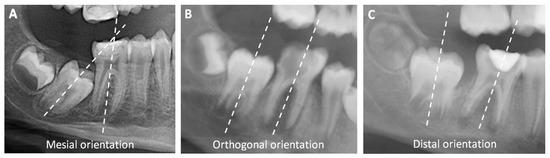

• For the mandible specifically, the mesial angulation of the SPM [10,13]. This criterion is evaluated using a radiograph, by tracing the SPM frontal axes of both FPM and SPM: if the axes cross at the coronal part, the angulation is mesial. If the axes are parallel, the angulation is orthogonal. If they cross at the apical part, the angulation is distal.

The author also collected the following data using a preoperative radiograph: the presence of TPM, the angulation of the SPM compared to the FPM (mesial, orthogonal, or distal) (Figure 1), and SPM Nolla’s stage.

The SPM angulation was never assessed when the decision involved a mandibular FPM. For the study, we assessed to SPM angulation with radiographs, except for six RCTs and six extractions where the radiograph was not large enough.

Figure 1. Orientations of mandibular SPM: (A) Mesial orientation, as the axes cross at the coronal part; (B) Orthogonal orientation, as the axes are parallel; (C) Distal orientation, as the axes cross at the apical part.